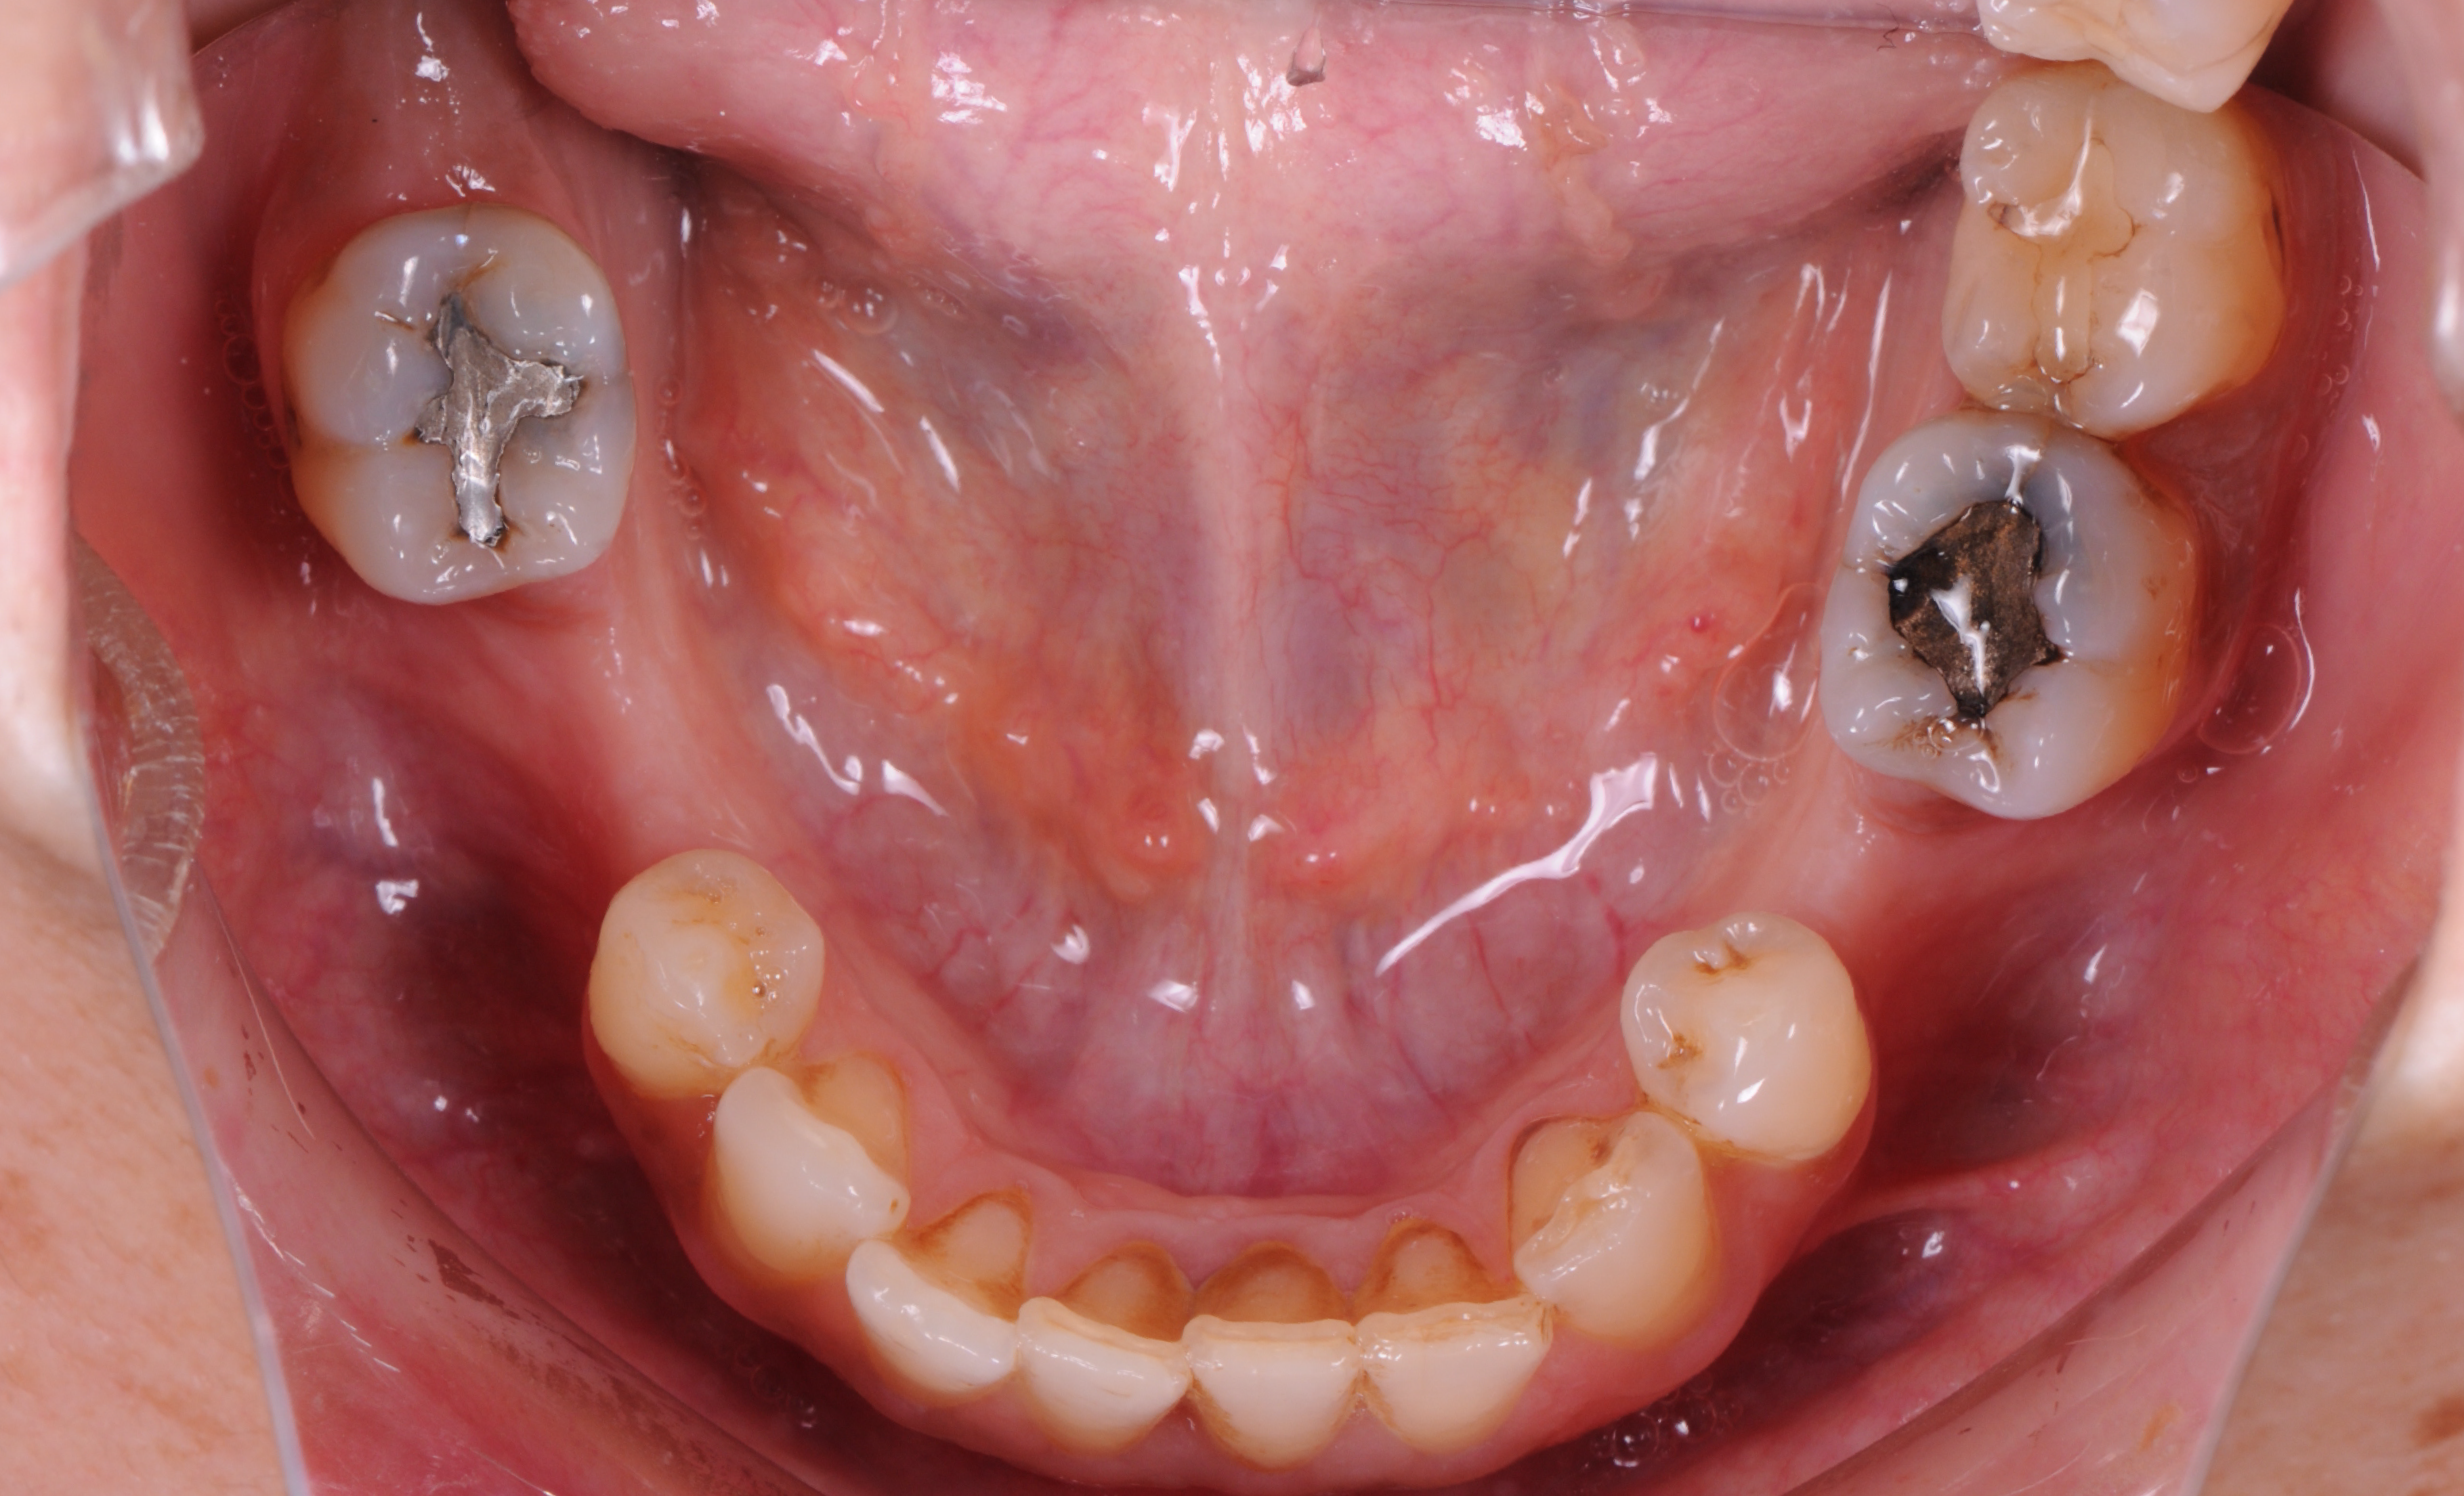

Estado inicial do dentes.